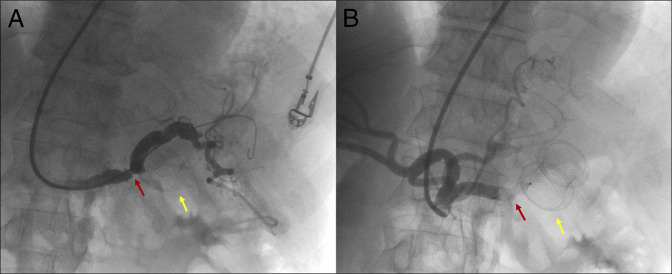

管腔旁置金属支架(LAMS)已被用于胰周收集物的引流,尽管它们可能伴有并发症,包括出血。我们报告一个49岁的男性病人,他出现呕血和晕厥后三周半的LAMS放置胰腺周围收集引流。计算机断层扫描显示脾动脉被支架远端法兰侵蚀。切除LAMS前行脾动脉栓塞术,3天后行脾切除术。患者在两年的随访后仍无症状。本病例展示了一种治疗罕见但可能致命的LAMS并发症的方法。

Lumen-apposing metal stents (LAMS) have been used for drainage of peripancreatic collections, although they may be associated with complications, including bleeding. We report a case of a 49-year-old male patient who developed hematemesis and syncope three and a half weeks after LAMS placement for peripancreatic collection drainage. A computed tomography scan revealed splenic artery erosion by the distal flange of the stent. Splenic artery embolization was performed before LAMS removal, and splenectomy was required 3 days later. The patient remains asymptomatic after two years of follow-up. This case demonstrates an approach to a rare but potentially fatal complication of LAMS.